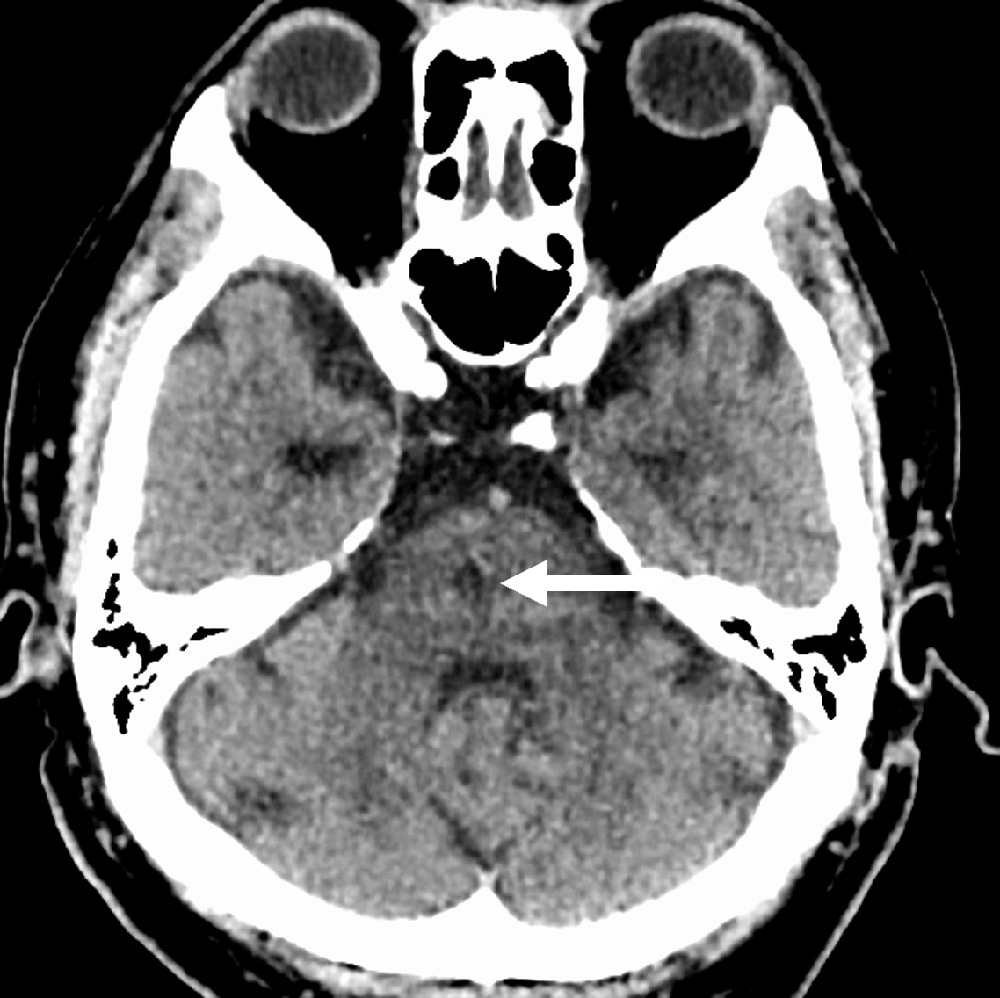

発症5日目に脳血管評価目的でCT angiographyの撮像依頼あり。MRI撮像ができないため、脳梗塞評価も兼ねて、全脳の多時相CT angiographyを撮像し、同一の収集データからCT perfusion画像も評価した。TIAの臨床診断であったが、単純CTとCT perfusionの所見から急性期~亜急性期ラクナ梗塞と診断した。

当該疾患の診断における造影CTの役割

急性期脳梗塞に対する血栓回収療法の適応判断においてCT perfusionの有用性が報告されている1-3)。CT perfusionは迅速にTmaxやCBFなどからischemic coreやpenumbraの評価が可能であり、また自動解析ソフトを用いることで客観的な定量評価が可能となる。320列CTで撮像すると、同じ撮影データから最適なCT angiographyやCT venography、多時相CT angiographyが再構成可能であり、脳梗塞の機序評価や血栓回収療法の治療戦略決定において有用である。本症例のようにMRI禁忌患者においては特にCT angiographyやCT perfusionが有用であった。